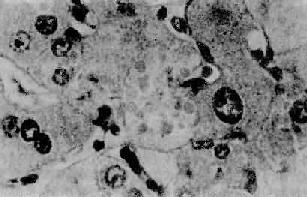

(2)乙型肝炎的发病机制:应用上述肝细胞免疫损伤机制可以解释乙型肝炎出现的不同类型:①T细胞功能正常,感染病毒量多,毒力强时受感染及免疫损伤的肝细胞多而重,表现为急性重型肝炎;②T细胞功能正常,病毒量较少,毒力较弱则发生急性普通型肝炎;③T细胞功能正常,病毒量甚少,毒力很弱则表现为轻型或亚临床型肝炎;④T细胞功能不足,免疫反应仅能清除部分病毒和损伤部分受感染的肝细胞,未清除的病毒可继续繁殖并感染,反复发生部分肝细胞损伤,结果表现为慢性肝炎;⑤机体免疫功能缺陷,T细胞呈免疫耐受状态,此时病毒与宿主共生。病毒在肝细胞内持续复制,感染的肝细胞也不受免疫损伤,此时则表现为无症状的病毒携带者。 四、酒精性肝病 酒精性肝病(alcoholic liver disease)为慢性酒精中毒的主要表现之一。长期大量酗酒者据统计有10%~20%发生此类损伤。严重时出现临床表现,如呕吐、呕血或黑便,其中部分可发生黄疸、肝功能衰竭。 病变 慢性酒精中毒主要引起肝的3种损伤,即脂肪肝、酒精性肝炎和酒精性肝硬变。三者可单独出现,也可同时并存或先后移行。一般认为脂肪肝在先,或经过酒精性肝炎再演变为肝硬变,或直接演变为肝硬变。 1.脂肪肝酒精中毒最常见的肝病变是脂肪变性。肝细胞含有相当大的脂滴,可将胞核推挤到细胞一侧,肝细胞肿大变圆。小叶中央区受累明显,有时同时伴有各种程度的肝细胞水样变性。单纯的脂肪肝常无症状。 2.酒精性肝炎(alcoholic hepatitis)在有临床肝症状表现的病例,常出现3种病变:肝细胞脂肪变性,酒精透明小体(alcoholic hyalin,AH 图10-42)形成和灶状肝细胞坏死伴中性粒细胞浸润。

图10-42 酒精性肝炎 图中央区肝细胞浆内见成群的酒精透明小体 ×400 3.酒精性肝硬变(alcoholic cirrhosis) 一般认为此种肝硬变是由脂肪肝和酒精性肝炎进展而来。一般的脂肪肝,如继续酗酒则多发展为酒精性炎,再演变为肝硬变。酒精性肝炎时肝细胞发生坏死,最终引起纤维化。相邻肝小叶的纤维化条索相互连接,导致肝小叶的正常结构被分割破坏,发展成假小叶及肝细胞结节状再生,形成酒精性肝硬变。 发病机制 肝是酒精代谢、降解的主要场所。酒精对肝有直接损伤作用。其机制如下: 1.NADH对NAD比值增高的效应进入肝内的酒精,在乙醇脱氢酶和微粒体乙醇氧化酶系的作用下转变为乙醛,再转变为乙酸。后一反应使辅酶Ⅰ(NAD)转变为还原型辅酶Ⅰ(NADH),因而NADH/NAD值增高。①NADH增多有抑制线粒体三羧酸循环的作用,从而使肝细胞对脂肪酸的氧化能力降低,可引起脂肪在肝内堆积而发生脂肪肝。②NADH增多可使细胞代谢中的乳酸增多,后者对肝内脂肪变及胶原形成等有促进作用。③NADH增多,使线粒体增加以NADH的再氧化,致耗氧过多。肝细胞因缺氧而易于发生坏死和纤维化。 2.乙醛的毒性作用在酒精代谢过程中产生的乙醛具有强烈的生化反应和毒性,可影响肝细胞膜的性状及抑制肝细胞合成的蛋白的分泌排出。 3.营养缺乏作用嗜酒者常有的营养不足,尤其是蛋白质缺乏,使肝内氨基酸及酶类减少,可以促进酒精的毒性作用。 五、肝硬变 肝硬变(liver cirrhosis)是一种常见的慢性肝病,可由多种原因引起。肝细胞弥漫性变性坏死,继而出现纤维组织增生和肝细胞结节状再生,这三种改变反复交错进行,结果肝小叶结构和血液循环途径逐渐被改建,使肝变形、变硬而形成肝硬变。本病早期可无明显症状,后期则出现一系列不同程度的门静脉高压和肝功能障碍。 肝硬变按病因分类为:病毒肝炎性、酒精性、胆汁性、隐源性肝硬变。按形态分类为:小结节型、大结节型、大小结节混合型及不全分隔型肝硬变(为肝内小叶结构尚未完全改建的早期硬变)。我国常用的分类是结合病因及病变的综合分类,分为:门脉性、坏死后性、胆汁性、淤血性、寄生虫性和色素性肝硬变等。以上除坏死后性相当于大结节及大小结节混合型外,其余均相当于小结节型。其中门脉性肝硬变最常见,其次为坏死后性肝硬变。其它类型较少。 (一)门脉性肝硬变 门脉性肝硬变(portal cirrhosis),旧称雷奈克(Laennec)肝硬变,相当于小结节型肝硬变。为各型肝硬变中最常见者。本病在欧美因长期酗酒者引起多见(酒精性肝硬变),在我国及日本,病毒性肝炎则可能是其主要原因(肝炎后肝硬变)。 病因和发病机制 1.病毒性肝炎慢性病毒性肝炎,尤以乙型慢性活动性肝炎是肝硬变的主要原因,其中大部分发展为门脉性肝硬变。在肝硬变患者肝内常显HBsAg阳性。其阳性率高达76.7%。另外,近年明确的丙型肝炎,大部可转为慢性,由慢性活动性肝炎转为肝硬变者达35%。 2.慢性酒精中毒在欧美国家因长期酗酒引起的肝硬变可占总数的40%~50%。 3.营养缺乏此项因素作为肝硬变的原因尚有争议。动物实验表明,饲喂缺乏胆碱或蛋氨酸食物的动物,可经过脂肪肝发展为肝硬变。 4.毒物中毒某些化学毒物对肝有破坏作用,长期作用可引起肝硬变。临床上偶有因含砷的杀虫剂、辛可芬、四氯化碳、黄磷等慢性中毒引起肝硬变的报告。 上述各种因素首先引起肝细胞脂肪变、坏死及炎症等,以后在坏死区发生胶原纤维增生。后者主要来自增生的纤维母细胞、局部的贮脂细胞及因肝细胞坏死,局部的网状纤维支架塌陷,网状纤维融合形成胶原纤维(无细胞硬化)。初期增生的纤维组织虽形成小的条索但尚未互相连接形成间隔而改建肝小叶结构时,称为肝纤维化。为可复性病变,如果病因消除,纤维化尚可被逐渐吸收。如果继续进展,小叶中央区和汇管区等处的纤维间隔互相连接,终于使肝小叶结构和血液循环被改建而形成肝硬变(图10-43)。